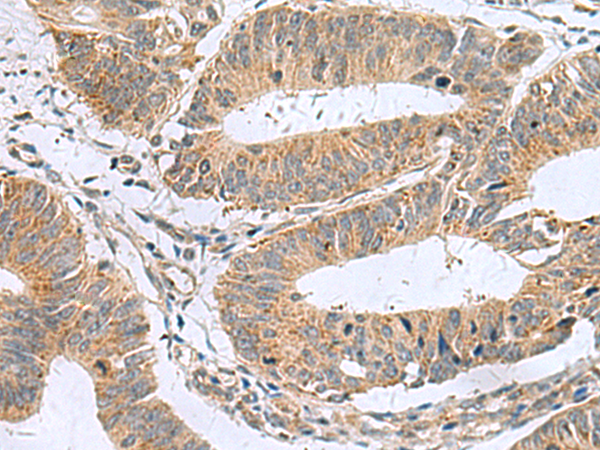

IHC positive control: |

Human colorectal cancer |

IHC Recommend dilution: |

50-100 |